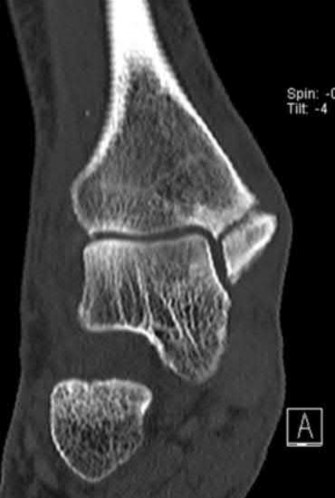

Question 9:

A 30-year-old male sustains a severe midfoot sprain. Radiographs reveal widening between the bases of the first and second metatarsals. The primary ligamentous stabilizer disrupted in this classic Lisfranc injury connects which two osseous structures?

Correct Answer: Medial cuneiform to 2nd metatarsal base

Explanation:

The Lisfranc ligament is the strongest ligament in the tarsometatarsal joint complex. It courses obliquely from the lateral aspect of the medial cuneiform to the medial base of the second metatarsal. It acts as the primary stabilizer of the second metatarsal base. Disruption results in the classic widening between the first and second rays, often with an avulsion fragment ('fleck sign').